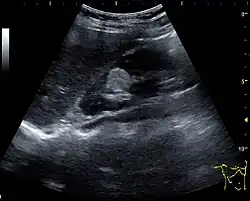

Three methods of scanning can detect angiomyolipomas: ultrasound, computed tomography (CT), and magnetic resonance imaging (MRI).[5] Ultrasound is standard and is particularly sensitive to the fat in angiomyolipomas, but less so to the solid components. However, accurate measurements are hard to make with ultrasound, particularly if the angiomyolipoma is near the surface of the kidney (grade III).[4] CT is very detailed and fast, and allows accurate measurement. However, it exposes the patient to radiation and the dangers that a contrast dye used to aid the scanning may itself harm the kidneys. MRI is safer than CT, but many patients (particularly those with the learning difficulties or behavioural problems found in tuberous sclerosis) require sedation or general anaesthesia, and the scan cannot be performed quickly.[3] Some other kidney tumours contain fat, so the presence of fat is not diagnostic. Distinguishing a fat-poor angiomyolipoma from a renal cell carcinoma (RCC) can be difficult.[6] Both minimal fat AMLs and 80% of the clear-cell type of RCCs display signal drop on an out-of-phase MRI sequence compared to in-phase.[7] Thus, a lesion growing at greater than 5 mm per year may warrant a biopsy for diagnosis.[3]